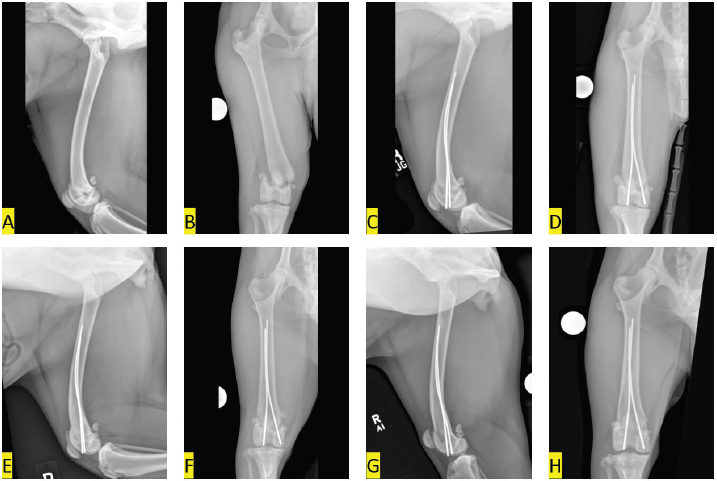

On initial evaluation, the dog was bright, alert, and responsive, but placed limited weight on the splinted right pelvic limb. The dog was sedated and the splint was removed. The right stifle was swollen and there was palpable instability and crepitus elicited on manipulation of the right distal femur. Radiographs of the right femur were obtained. There was a sharply margined fracture that extended through the right distal femoral physis which included a small angular portion of the caudomedial aspect of the distal femoral metaphysis (Salter-Harris type II injury). The distal fracture segment was laterally and slightly caudally displaced. The soft tissues along the medial aspect of the distal femur were moderately thickened (Fig. 1A and B). Surgery was scheduled for the following day.

Radiographic images of the right femur were obtained immediately following surgery. The reduction was near anatomic as there was mild widening of the caudomedial aspects of the physis. The Steinmann pins were placed appropriately in Rush fashion. There was a mild increase in soft tissue opacity in the stifle joint, compared to preoperative radiographs, likely due to hemorrhage, and the soft tissues surrounding the distal femur remained thickened (Fig. 1C and D). The dog was intermittently placing weight on the right pelvic limb when discharged the day following surgery. The owners were instructed to keep the dog confined to a crate or small room when unattended and restrict the dog’s outdoor activities to short walks on a leash for the first 4 weeks following surgery. Performing passive range of motion exercises on the right stifle was also recommended.

The dog was re-evaluated 5 weeks following surgery at which time the owner felt the dog was comfortable and using the right pelvic limb normally. On the orthopedic examination, the dog did not have a discernable lameness. Range of motion in the right stifle was only slightly reduced and pain was not elicited on flexion or extension. Radiographically, reduction was unchanged and the fracture margins were ill-defined, indicative of early healing. Along the medial aspect of the distal femoral metaphysis, there was a triangular region of smooth osseous proliferation ascribed to periosteal disruption. The Steinman pin in the lateral femoral condyle extended 1 mm distal to the margin of the subchondral bone, but the position of the implants appeared otherwise unchanged. Joint effusion and soft tissue swelling had resolved (Fig. 1E and F). The owners were advised to continue activity restriction for another 2 weeks before the dog could resume normal activities.

The dog was re-evaluated 9 months after surgery. The owner stated that the dog had resumed all normal activities without appreciable lameness and was very satisfied with the surgical outcome. On examination, the dog was not obviously lame. Force plate analysis was performed and peak vertical force was 12% less in the left pelvic limb than the right pelvic limb. There was full range of motion of the right stifle and no pain was elicited on flexion or extension. Goniometry was performed under sedation and flexion of the right stifle measured 30°, compared to 28° in the left stifle. Extension of the right stifle measured 168°, compared to 166° in the left stifle. Thigh circumference measured 39.6 cm and 39.2 cm in the right and left pelvic limbs, respectively. Radiographs confirmed complete union of the previously described fracture with minimal stifle osteoarthrosis and unchanged implants (Fig. 1G and H).

Fig. 1. Mediolateral (A, C, E, G) and caudocranial (B, D, F, H) radiographic images of the right femur. (A, B) pre-operative images show a laterally and slightly caudally displaced Salter-Harris type II fracture of the distal femur; (C, D) immediate post-operative images show the distal epiphysis has been nearly anatomically reduced. Two Steinmann pins have been placed in Rush fashion to stabilize the reduced fracture; (E, F) 5-weeks post-operative images of the right femur show the fracture remains reduced and aligned. The fracture margins are ill-defined, indicative of early healing. The Steinman pin in the lateral femoral condyle extends 1 mm distal to the lateral femoral condylar margin, but position of the implants seems otherwise unchanged; (G, H) 9-months postoperative images of the right femur show complete healing of the fracture with nominal stifle osteoarthrosis.